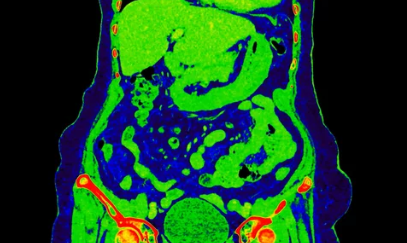

4. 장폐색 & 장유착, 어떻게 진단하나요? 영상 검사와 혈액 검사

장폐색과 장유착은 환자의 증상, 병력, 신체 검사 결과를 종합적으로 고려하여 진단합니다. 복부 X-ray, CT, MRI 등 영상 검사를 통해 장 폐쇄 부위와 원인을 확인하고, 혈액 검사를 통해 염증 수치, 전해질 불균형 등을 확인합니다.

- 복부 X-ray: 장 내 가스 분포를 확인하여 장 폐쇄 여부를 진단합니다.

- CT (컴퓨터 단층촬영): 장 폐쇄 부위와 원인을 더욱 정확하게 확인할 수 있습니다.

- MRI (자기공명영상): CT보다 연부 조직을 더욱 자세히 볼 수 있어 장유착 진단에 유용합니다.

- 혈액 검사: 염증 수치 (백혈구 수치, CRP 등), 전해질 불균형 등을 확인합니다.